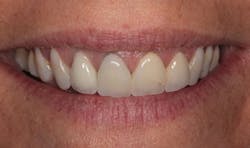

In Figure 1, you can see a close-up view of her smile as it was when she presented. She recently had noticed a fracture in both central incisor crowns and, since replacement was necessary, wanted to investigate the possibilities for improvement. The retracted facial view can be seen in Figure 2. Clinical and radiographic examination showed me that her overall dental health was good, with no periodontal disease or active caries. The patient expressed an interest in widening her smile and achieving a lighter color. The shade she desired was OM1 on the Vita Toothguide 3D-Master shade guide (figure 3).

Figure 3: The patient’s desired shade compared to her initial smile